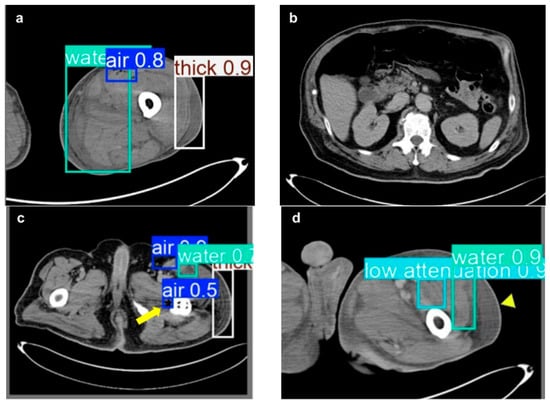

| NSTI features | ||

| Soft tissue ectopic gas | 1982 | 33.13% |

| Fluid accumulation | 1577 | 27.04% |

| Fascia edematous changes | 1872 | 32.10% |

| Soft tissue non-enhancement | 401 | 6.88% |